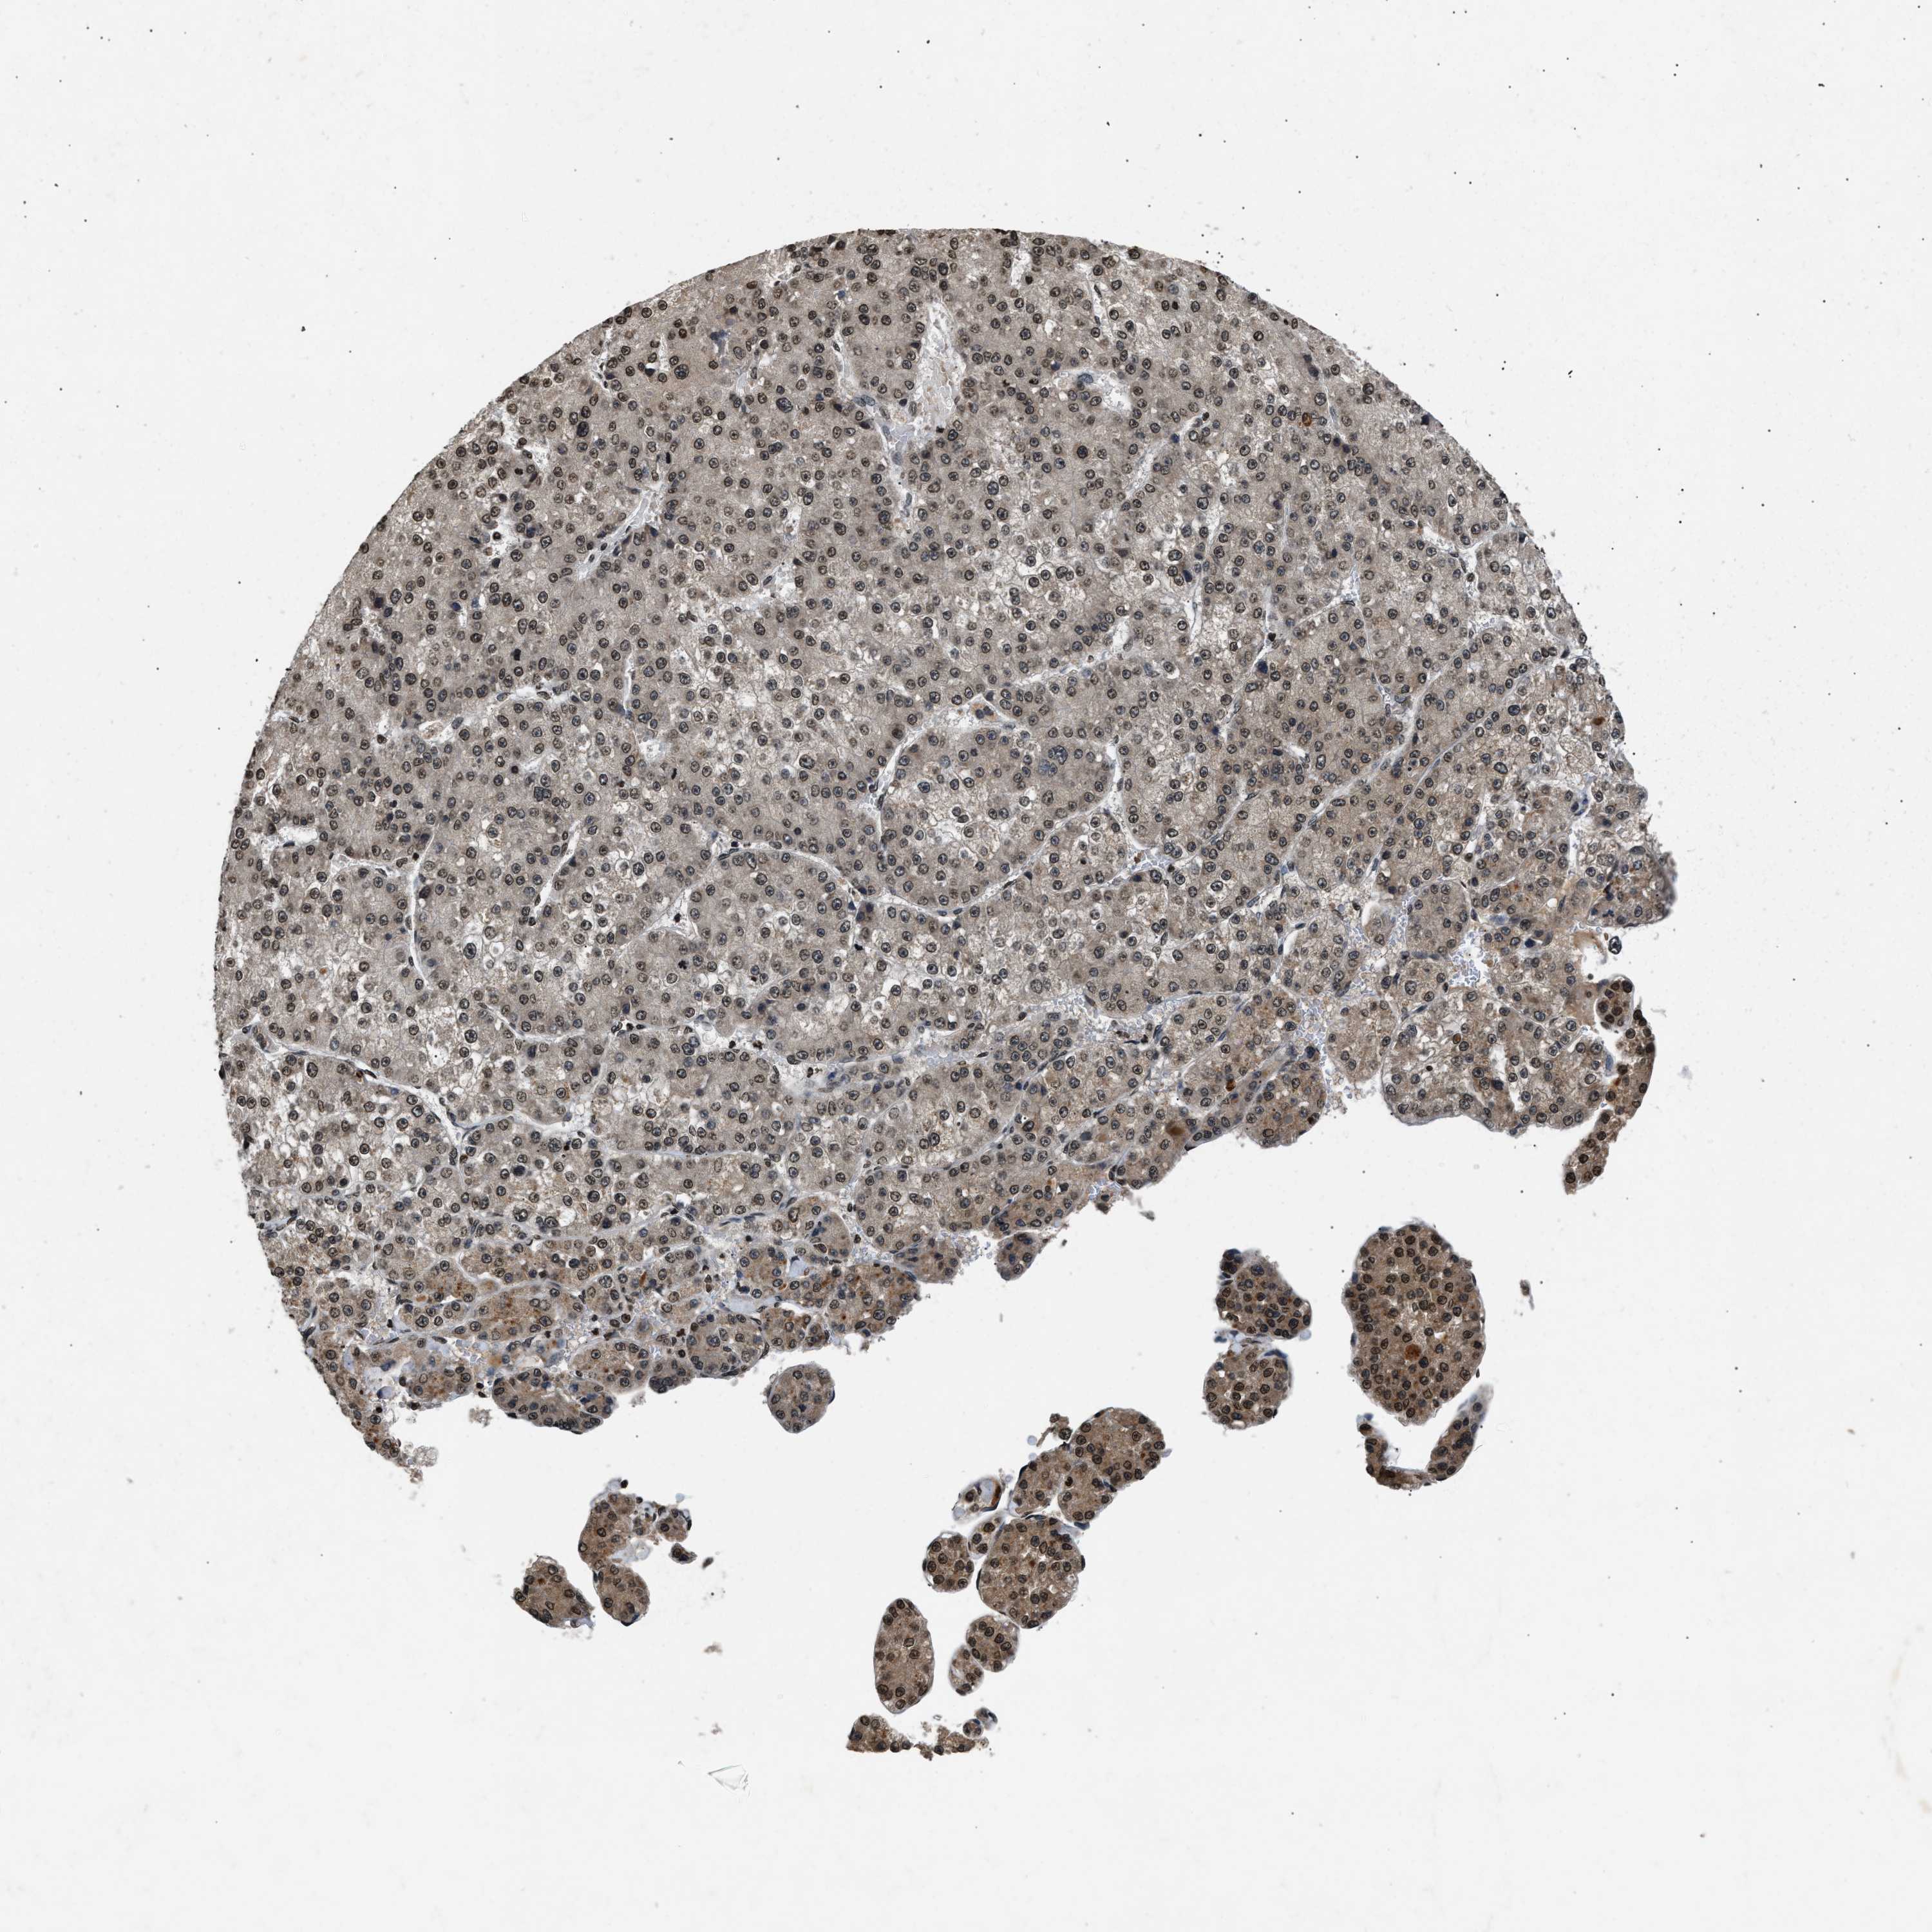

LIVER CANCER - Protein expressioni

A mouse-over function shows sample information and annotation data. Click on an image to view it in a full screen mode. Samples can be filtered based on level of antibody staining by selecting one or several of the following categories: high, medium, low and not detected. The assay and annotation is described here.

Note that samples used for immunohistochemistry by the Human Protein Atlas do not correspond to samples in the TCGA dataset.

Antibody stainingi

Antibody staining in the annotated cell types in the current human tissue is reported as not detected, low, medium, or high, based on conventional immunohistochemistry profiling in selected tissues. This score is based on the combination of the staining intensity and fraction of stained cells.

Each image is clickable and will lead to virtual microscopy that enables deeper exploration of all samples and also displays staining intensity scores, fraction scores and subcellular localization as well as patient and tissue information for each sample.

Antibody HPA019955

Staining

High

Medium

Low

Not detected

Intensity

Strong

Moderate

Weak

Negative

Quantity

>75%

75%-25%

<25%

None

Location

Nuclear

Cytoplasmic/membranous

Cytoplasmic/membranous,nuclear

Cholangiocarcinoma

Carcinoma, Hepatocellular, NOS